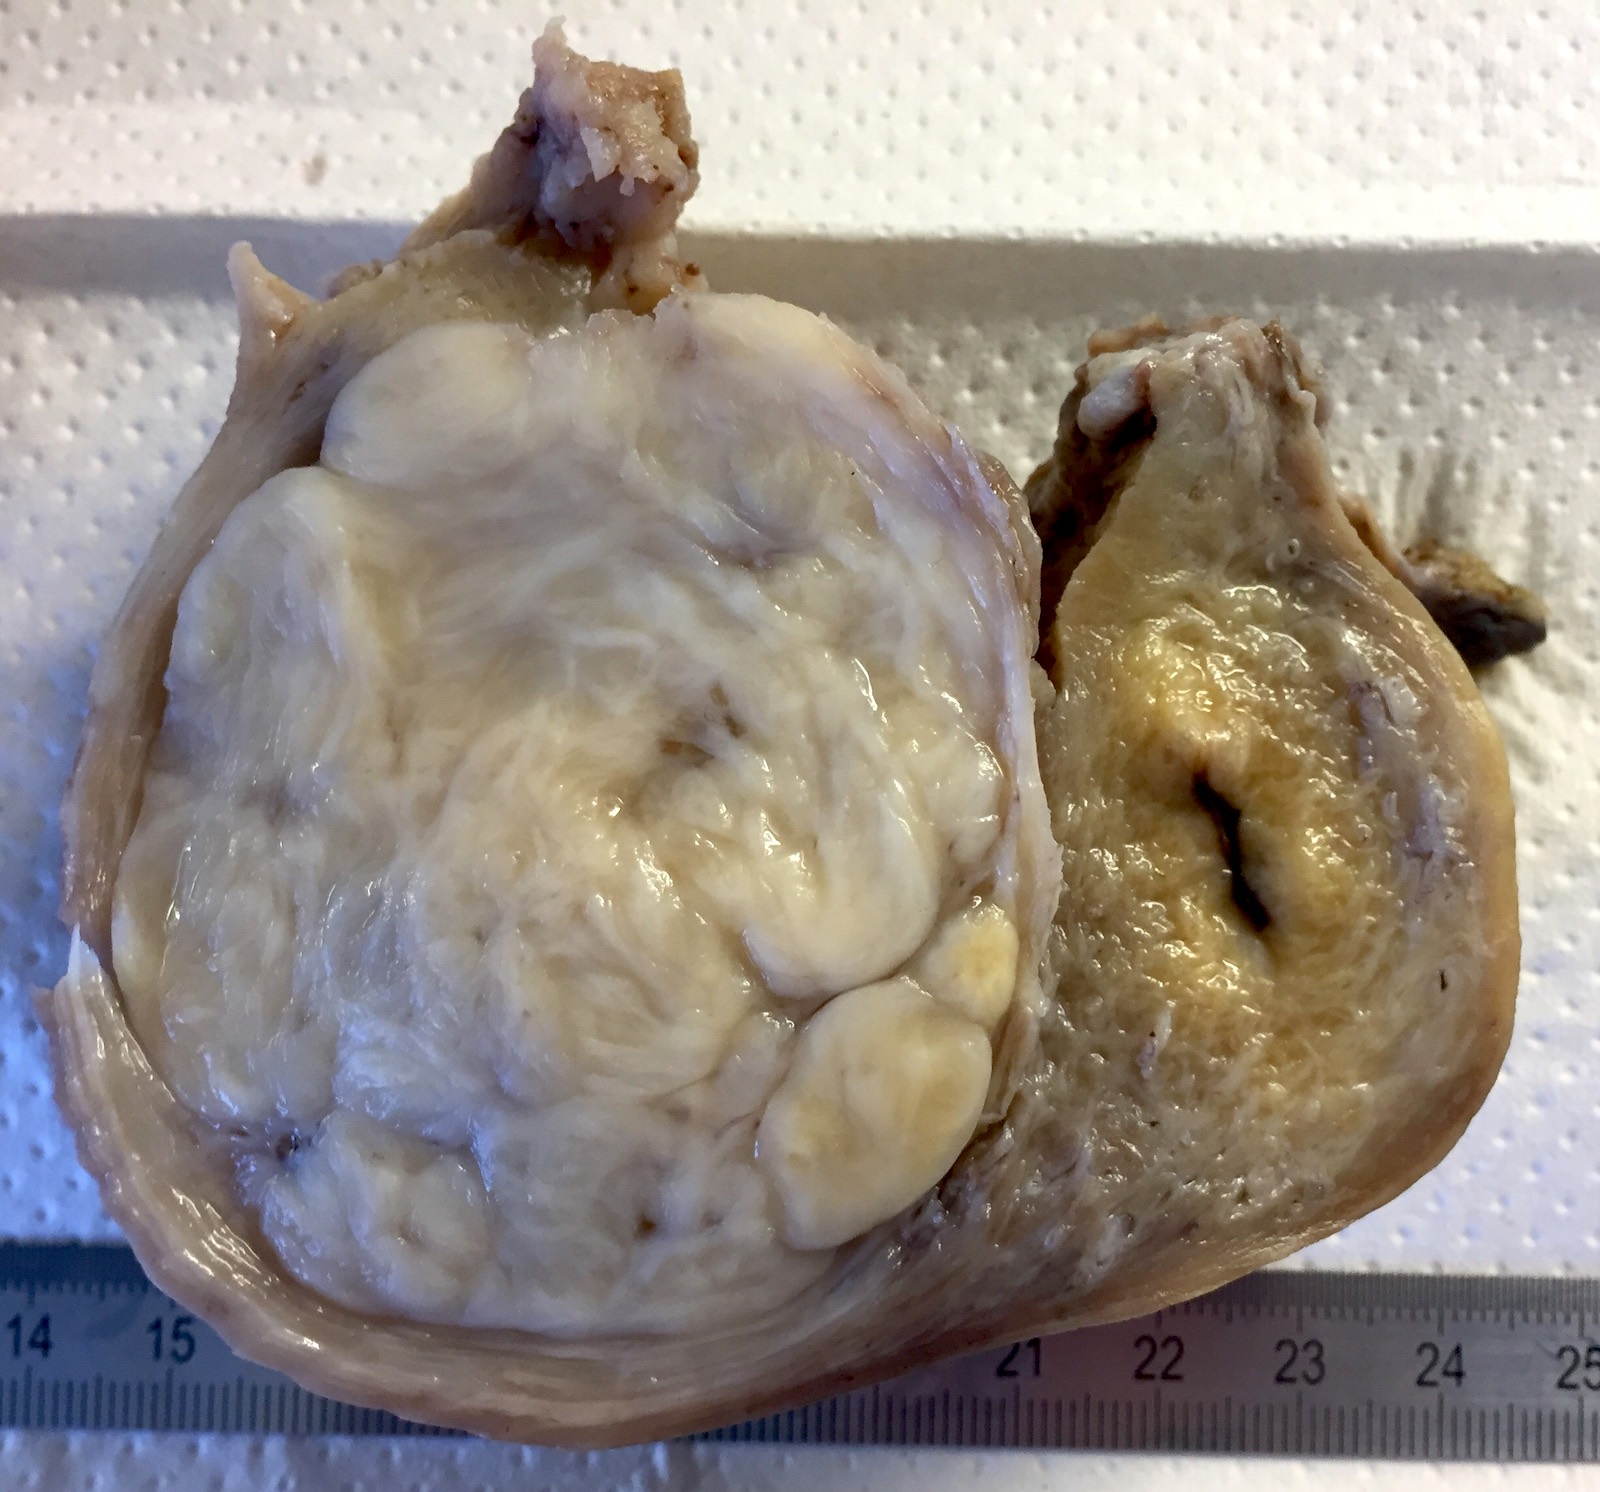

Gross description

- Location in the uterus: intramural, submucosal and subserosal

- Often multiple

- Typically well circumscribed but nonencapsulated

- On cut surface: white or tan-white, whorled, firm, bulging

- Hemorrhage and infarction can be present in large tumors

- Calcifications can be present

- Apoplectic change (foci of hemorrhage) associated with progesterone therapy

- Extensive sampling (to exclude malignancy)

- Especially in leiomyomas that lack the classic gross appearance

- Myxoid areas to exclude myxoid leiomyosarcoma

- Reference: Mod Pathol 2016;29:S104

Gross images